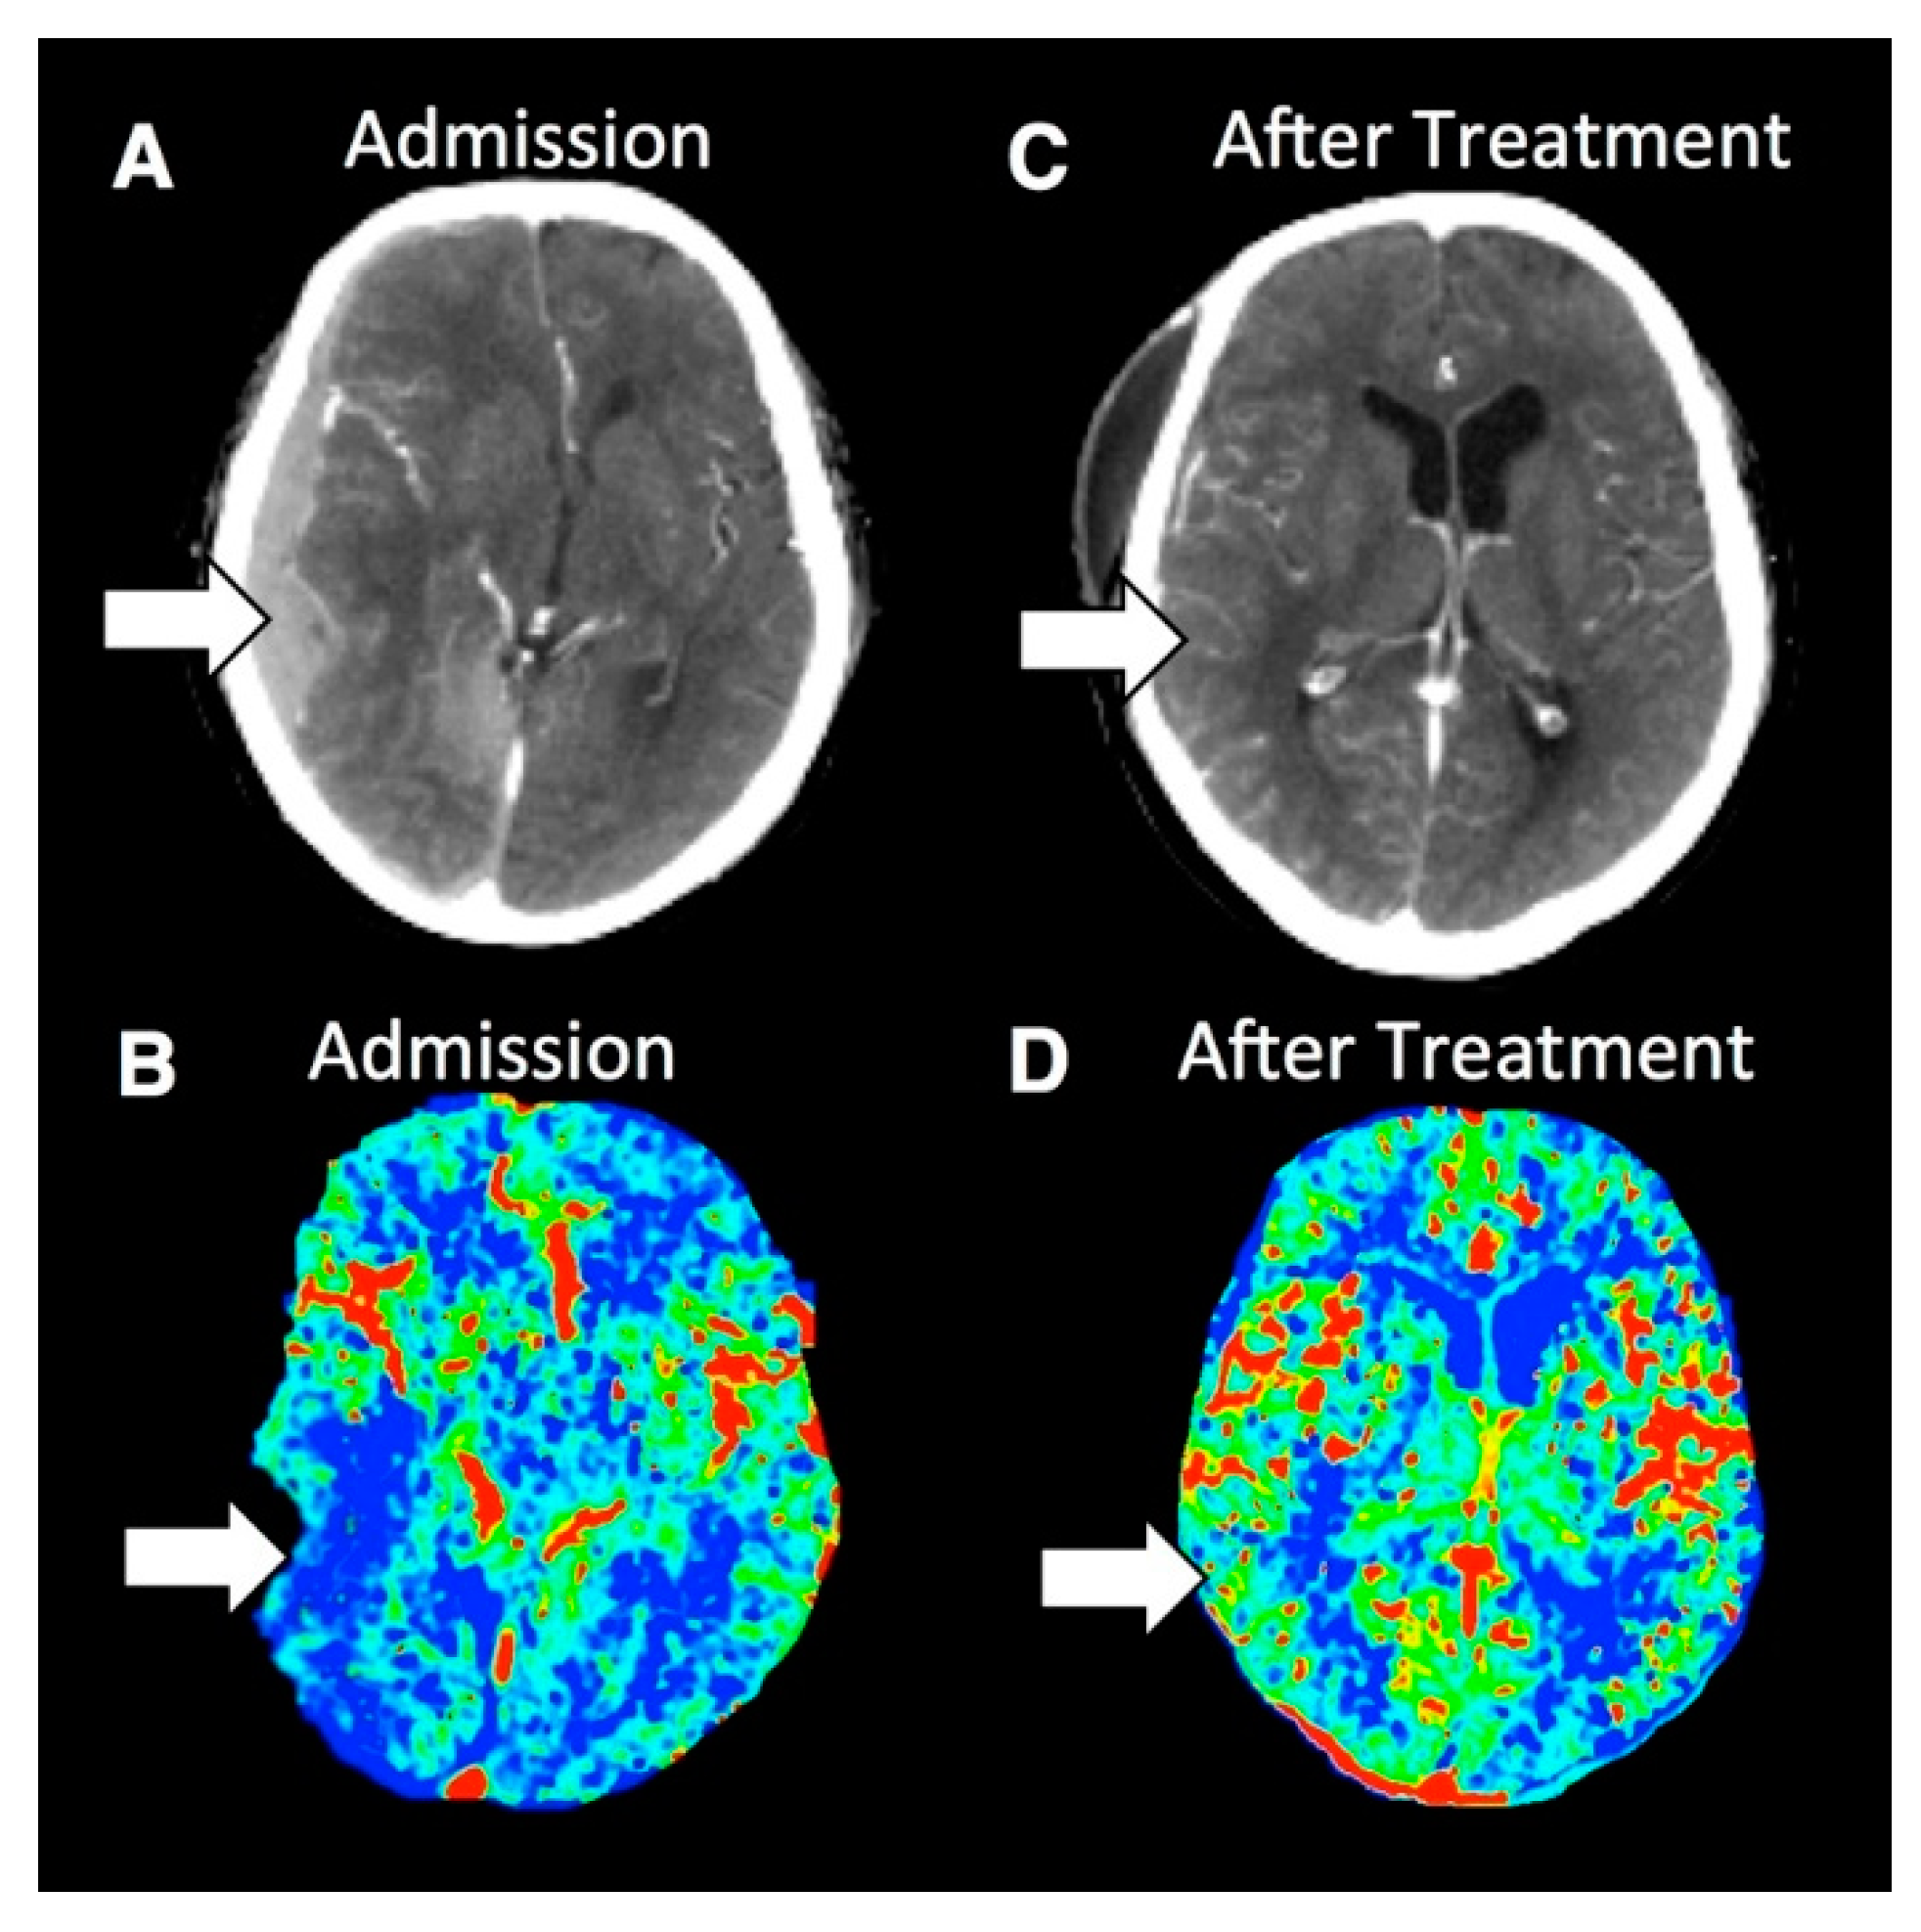

28+ Brain Treatment Center Reviews PNG. Mert changed everything for us. i'm two or three months past my last treatment, and i can honestly say my brain is in a better place than it was before. While the neuromodulation equipment used in the mertsm process has been cleared by the fda in the.

Patients come to alvord brain tumor center from across the country for treatment of all spinal cord and brain cancers. Contact houston methodist to learn more. La directora de brain treatment center panamá, la sra.

Doctor in newport beach, california. The brain treatment centre uses a multimodal program to address both brain conditions as well as peak brain performance. Brain tumor treatment in leading medical centres abroad. Work at brain treatment center?